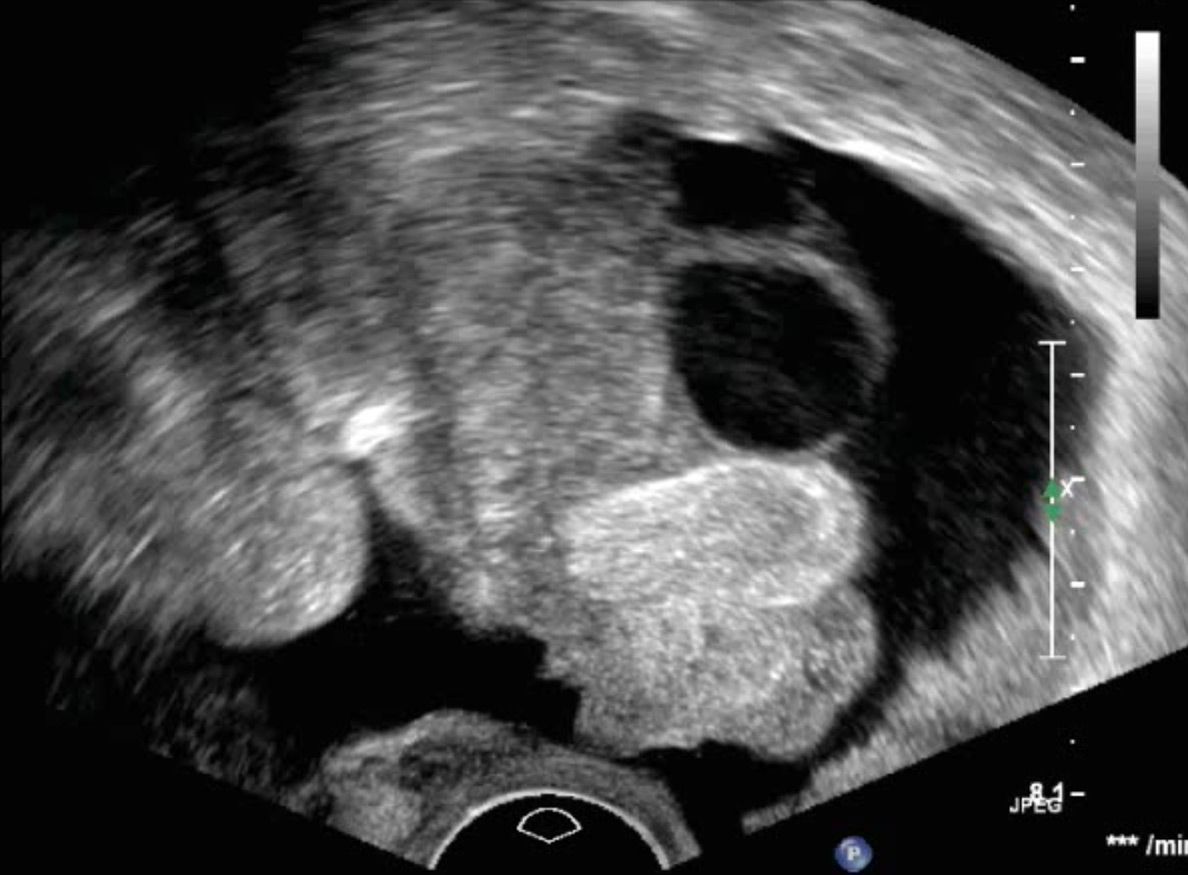

Ovarialkarzinom

Veränderungen des Eierstocks sind gerade vor den Wechseljahren häufig funktioneller Natur und durch zyklusbedingte Einflüsse zu erklären. Diese sollten nicht beunruhigen und sind in aller Regel im natürlichen Verlauf abzuwarten. Raumforderungen am Eierstock können aber auch Beschwerden hervorrufen. Zum anderen sollten sie gegen bösartige Veränderungen abgegrenzt werden. Letztere sind selten, jedoch von ungünstiger Prognose, wenn sie ein fortgeschrittenes Stadium erreicht haben.

Die Abgrenzung zwischen einer einfachen funktionellen Veränderung, einer gutartigen Veränderung oder einer potentiell bösartigen Veränderung sollte primär sonographisch erfolgen.